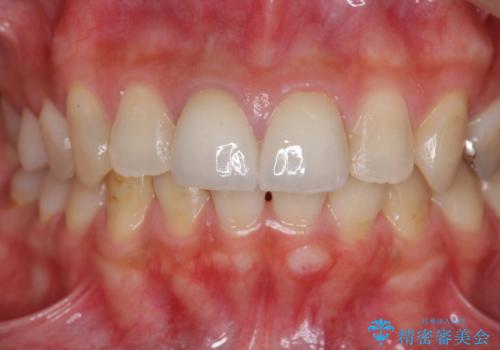

- 前歯の見た目、変色の改善を希望され来院されました。

ジルコニアクラウンによる審美性の改善を計画します。

神経の治療をした歯について

神経をとる治療を行った歯は、時間が経過すると術前のように変色し見た目を大きく損ないます。

このような場合金属を使わないジルコニアクラウンを用いた治療を行うことで天然の歯のように審美性を改善することが可能になります。